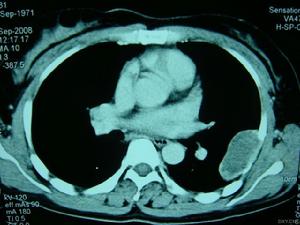

在制定手術方案時,須精確確定腫瘤在骨髓腔內或松質骨內的侵襲範圍,可藉助於骨掃描、CT和MRI。

中心性軟骨肉瘤傾向於向阻力較小的地方擴張,如骨幹的髓腔。在幾乎一半的病例中,放射影像顯示腫瘤侵犯整個長骨的1/3、1/2或更多,但在腫瘤早期,影像上可能無顯示。這個特點很重要,否則手術方案可能不恰當,切除緣可能不夠,於骨幹切除或截肢術後殘肢處腫瘤可復發,為避免發生,須在術前通過骨掃描、CT和MRI來確定腫瘤在髓腔內的範圍。